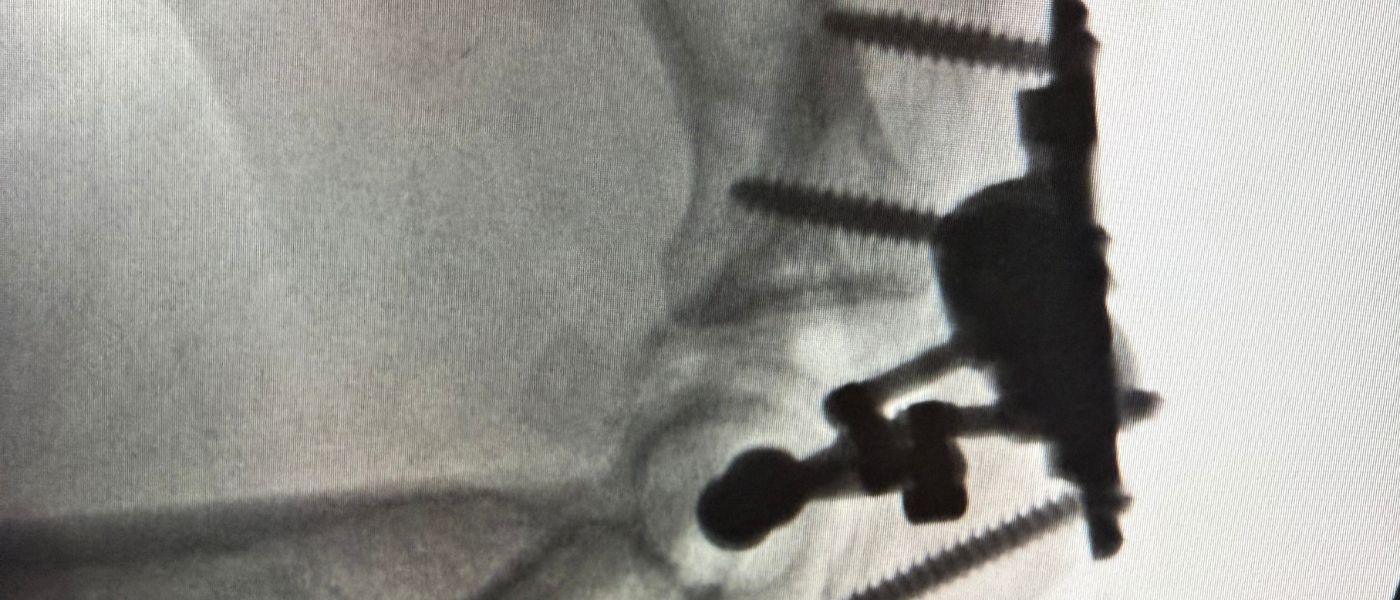

The purpose of joint replacement is to remove damaged and diseased parts of the joint, replacing them with new, artificial hardware. The replacement of these joints is meant to improve quality-of-life significantly and offer the patient lasting relief from joint pain and disability. With modern technology and techniques, the risks of joint replacement surgery are significantly lower than ever before. Further, with proper care, artificial joints can last for decades – and for many patients, the rest of their lives. Virtually any joint in the body can be replaced, most commonly:

When cartilage restoration is no longer an option, joint replacement can restore function and quality of life.